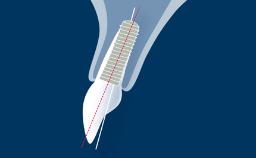

O momento em que os implantes são colocados em função é marcado pela conexão da prótese ao implante. A escolha do protocolo de carregamento mais adequado é um passo importante no processo de planejamento do tratamento. Ao selecionar o momento da reabilitação com implante, você se depara com uma importante decisão clínica. Este módulo apresenta os diferentes critérios para escolher os protocolos de carregamento.

- listar as definições de protocolos de carregamento de implantes imediatos, precoces e convencionais